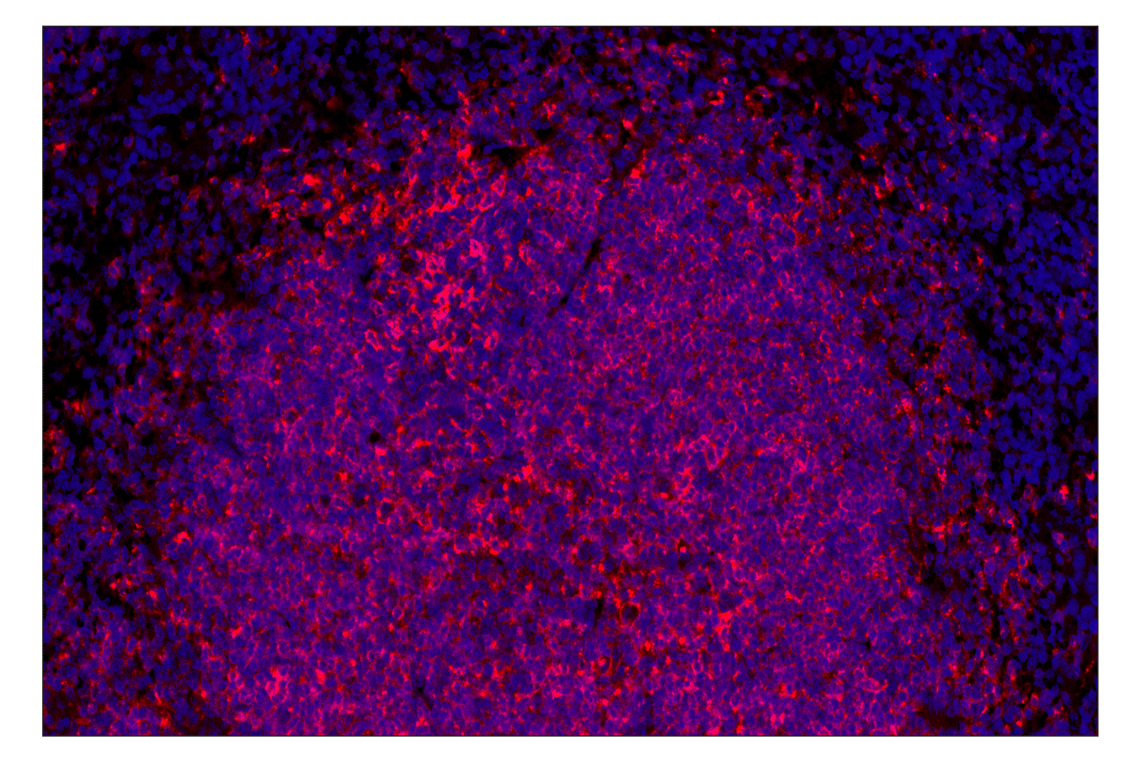

MHC Class II (I-E alpha) (F8N7J) Rabbit Monoclonal Antibody (Alexa Fluor® 647 Conjugate) #49980

MHC Class II (I-E alpha) (F8N7J) Rabbit Monoclonal Antibody (Alexa Fluor® 647 Conjugate) recognizes endogenous levels of total MHC Class II (I-Eα) protein. This antibody does not cross-react with MHC Class II (I-Aα) protein.

Immunohistochemistry (Paraffin) 1:50 - 1:200